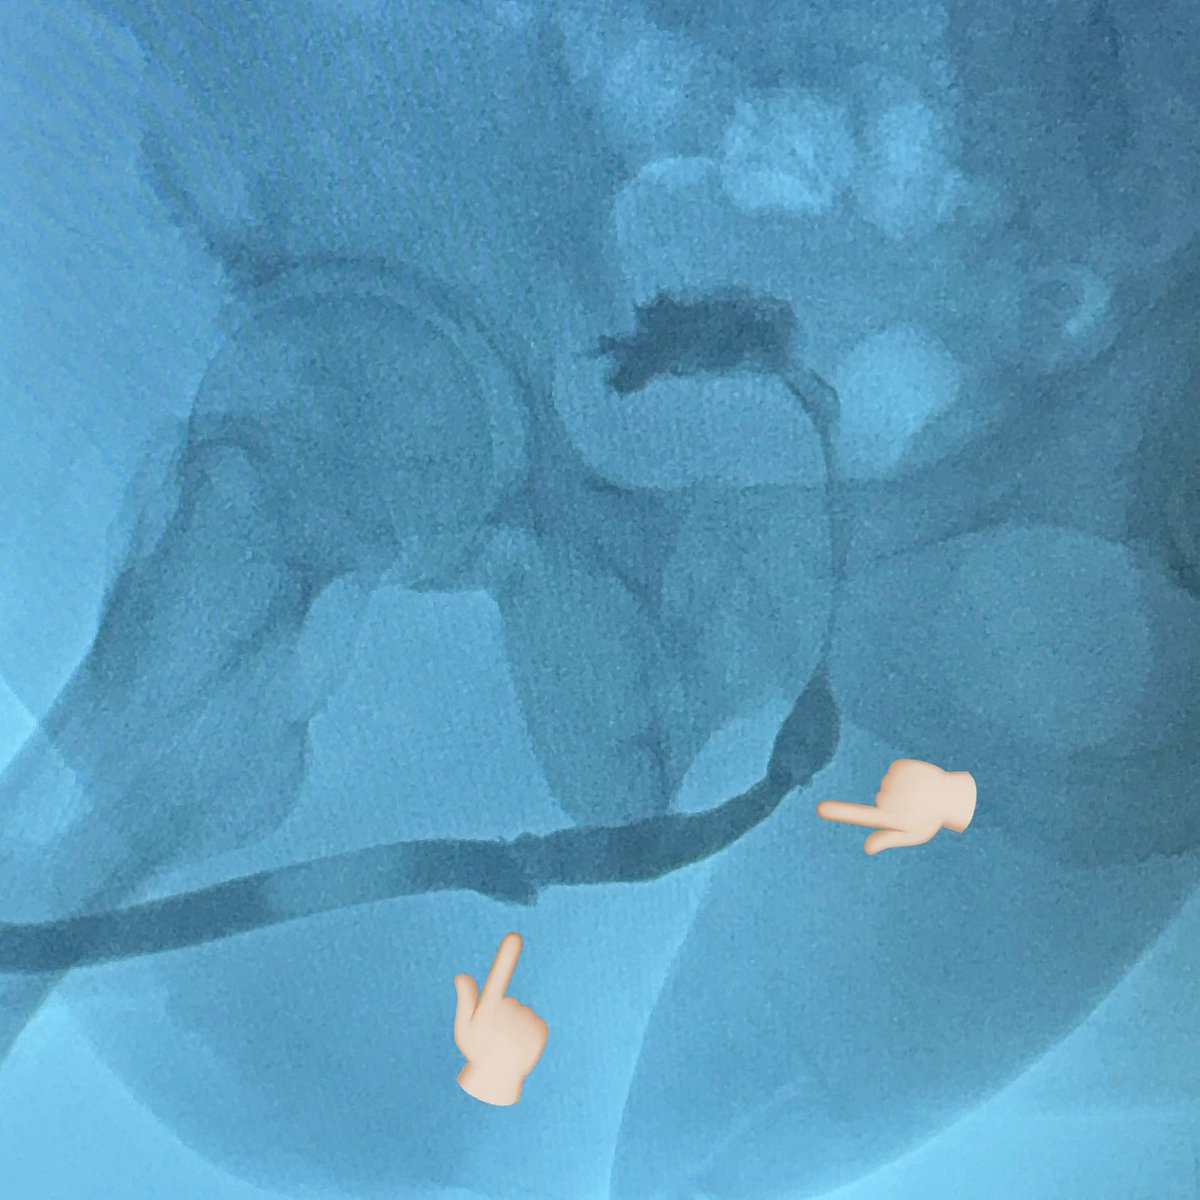

It's an old technique but once you don't have enough urethra to anastomose or augment, pedicled penile skin flap-tube might be the best option left. We also did hyperbaric oxygen therapy (HBOT), which probably helped a-lot. Mark (Toto) Abalajon MD #redourethroplasty #Pedicledskinflap

It's an old technique but once you don't have enough urethra to anastomose or augment, pedicled penile skin flap-tube might be the best option left. We also did hyperbaric oxygen therapy (HBOT), which probably helped a-lot. <a href="/abalajontoto/">Mark (Toto) Abalajon MD</a> #redourethroplasty #Pedicledskinflap